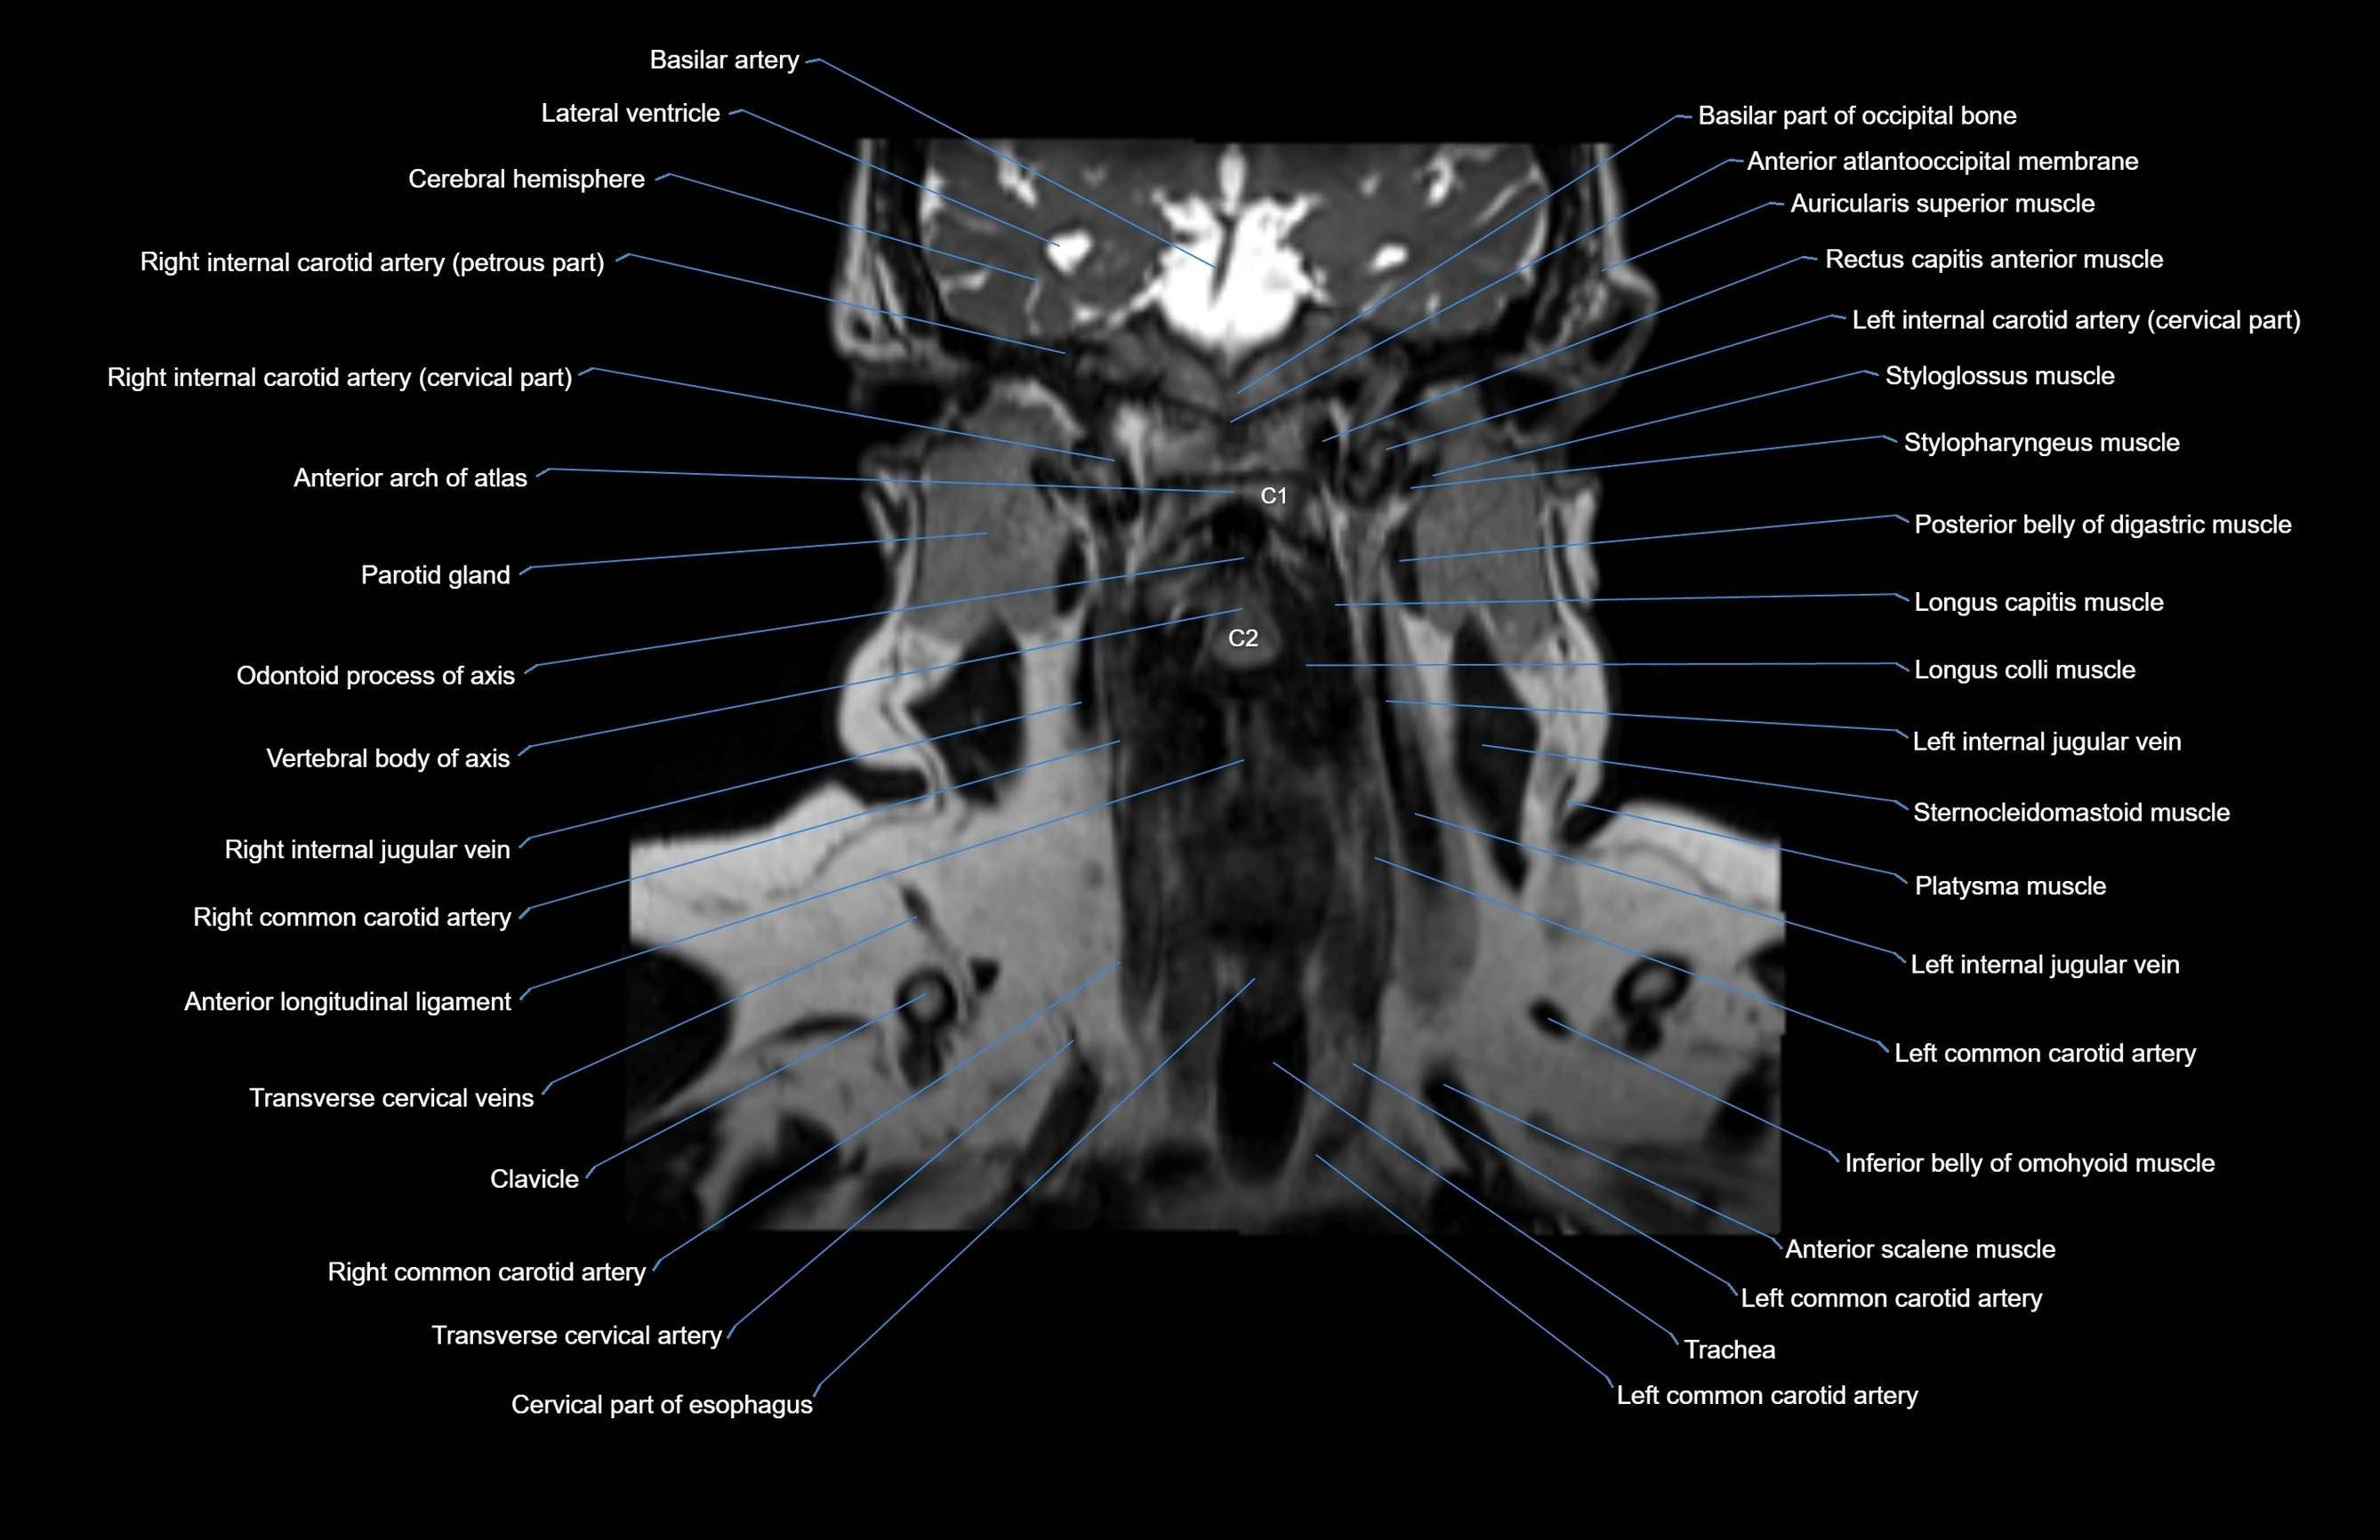

- Anterior arch of atlas

- Anterior atlanto-occipital membrane

- Anterior longitudinal ligament

- Axis (C2 vertebra)

- Clavicle

- Common carotid artery

- Inferior belly of omohyoid muscle

- Internal carotid artery (cervical part)

- Left common carotid artery

- Longus capitis muscle

- Longus colli muscle

- Odontoid process

- Parotid gland

- Platysma muscle

- Posterior belly of digastric muscle

- Sternocleidomastoid muscle

- Styloglossus muscle

- Stylopharyngeus muscle

- Trachea

- Transverse cervical artery